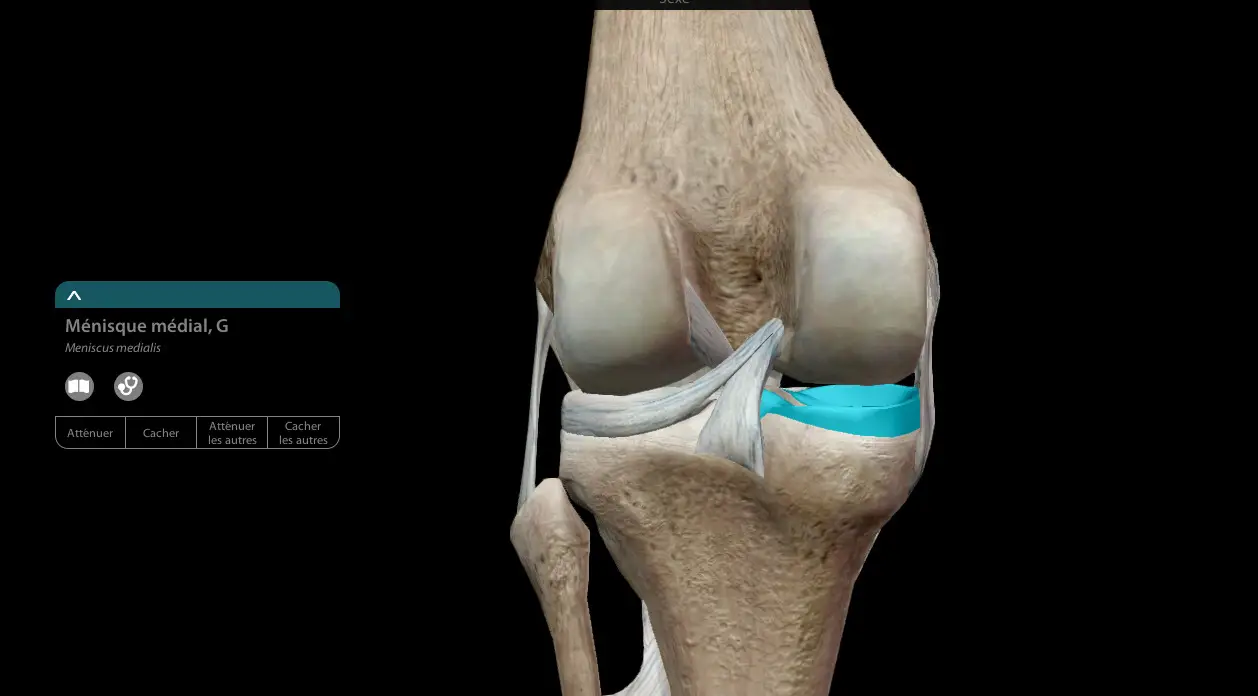

Comme nous l'avions évoqué lors de la présentation de la rupture du ligament croisé, le genou est une articulation complexe composée de diverses structures (os, ligaments, muscles, liquide synovial...) Parmi celles-ci, on retrouve les ménisques. Au nombre de deux, ils recouvrent la partie supérieure du tibia.

Le fémur étant "arrondi", et le tibia "plat", les ménisques sont présents au milieu dans le but de combler l'espace. Leur rôle permet d'amortir les chocs, car l'articulation du genou est globalement très sollicitée. Ils ont aussi un rôle de stabilisateur, parce qu'ils empêchent le genou de sortir de son axe. Il est possible de vivre sans ménisques, mais le processus de gonarthrose sera accéléré.

On retrouve deux ménisques situés de part et d'autre de la rotule :

- Le ménisque interne ou médial situé à proximité de l'autre jambe

- Le ménisque externe ou latéral, regardant vers l'extérieur.

Leur rôle est essentiel dans la stabilisation du genou avec les ligaments croisés. Leur large structure permet de mieux répartir les pressions exercées sur le genou. Lors de mouvements de course et de pivot, le poids exercé sur notre articulation est très important, surtout lorsque l'on se retrouve sur un appui unipodal. Leur structure élastique va faciliter le mouvement de flexion et extension du genou.